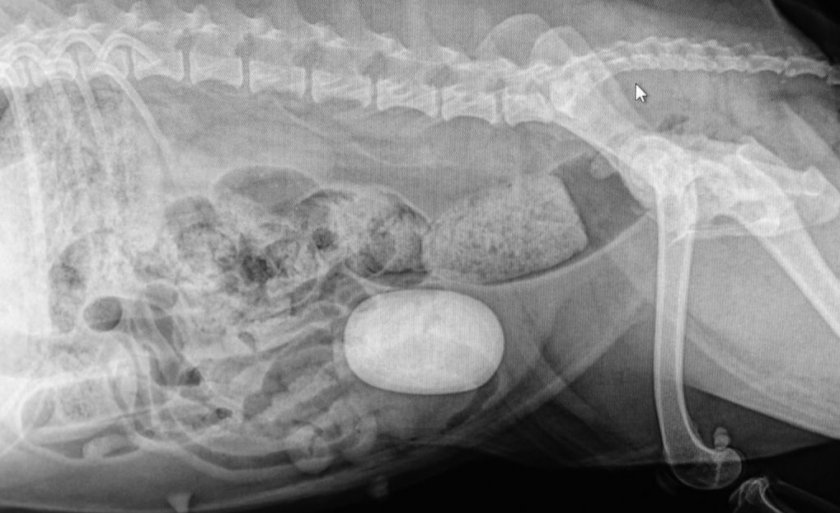

Для постановки точного диагноза больной питомице проводят УЗИ, назначают рентгенографию и берут мазок из половых органов. При внешнем осмотре ветеринар может заметить увеличение матки и её болезненность при пальпации.

Насторожить хозяина должно беспокойное поведение питомца, потребление большого количества воды, частые позывы в туалет и отказ от пищи. Нередко наблюдается повышение температуры тела. Примечательно, что первые признаки недуга у кобелей становятся заметными гораздо раньше, чем у сук, а развитие болезни проходит намного острее, ввиду анатомических особенностей мочеполовой системы. В целом, признаки наличия камней в почках во многом схожи с симптомами цистита и пиелонефрита, поэтому для постановки окончательного диагноза стоит провести расширенное обследование, с применением разных диагностических методов.